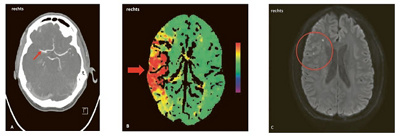

Die Akutdiagnostik beginnt sofort nach Eintreffen auf der Notfallstation mit der klinisch-neurologischen Untersuchung durch einen auf Schlaganfälle spezialisierten Neurologen, um die potenziellen neurologischen Defizite zu erfassen. Die zweite Säule der Akutdiagnostik bildet die radiologische (bildgebende) Untersuchung des Gehirns anhand einer Computertomographie (CT) oder einer Kernspintomographie (MRI) (vgl. Abb. 2). Dadurch kann zwischen dem ischämischen und dem hämorrhagischen Schlaganfall unterschieden werden, was für die anschliessende Therapie entscheidend ist. Im gleichen Zug wird das Gefässsystem der hirnversorgenden Arterien untersucht und geklärt, ob bzw. wo ein Gefässverschluss durch ein Gerinnsel vorliegt oder wo die Blutungsquelle bei einer Hirnblutung zu finden ist.

Abb. 2: Die in der Akutdiagnostik durchgeführte Computertomographie mit Gefässdarstellung (CT-Angiographie) zeigte einen akuten Verschluss der mittleren Gehirnarterie (Arteria cerebri media) rechts durch ein Gerinnsel (Abb. 2a, Pfeil). Dieser Gefässverschluss führte zu einer kritischen Minderdurchblutung der rechten Gehirnhälfte im Versorgungsgebiet der mittleren Gehirnarterie (Abb. 2b, dicker Pfeil: rotes Areal). Es bestand eine hochgradige Lähmung der linken Körperhälfte. Nach erfolgter Akuttherapie mittels intravenöser Thrombolyse und Katheter gestützter Entfernung des Gerinnsels (Thrombektomie) konnte die Durchblutung wiederhergestellt und ein grösserer ischämischer Schlaganfall verhindert werden. Es zeigten sich im MRI nach der Akuttherapie lediglich winzige umschriebene ischämische Areale (Abb. 2c, Kreis: weisse Punkte). Der Patient war ohne Symptome nach der Therapie, eine Lähmung bestand nicht mehr.

über die Vene verabreicht. Bei Verschluss einer grösseren Gehirnarterie, was oft mit schweren neurologischen Symptomen einhergeht, da grössere Bereiche des Gehirns minderdurchblutet sind, kann das Gerinnsel alternativ oder ergänzend mithilfe eines von der Leiste bis zur verschlossenen Gehirnarterie vorgeschobenen Katheters entfernt werden (Thrombektomie). Eine solche Behandlung ist nur in einem zertifizierten Stroke Center möglich, weshalb insbesondere schwer betroffene Patienten nach Möglichkeit direkt dem nächstgelegenen Stroke Center zugewiesen werden sollten.